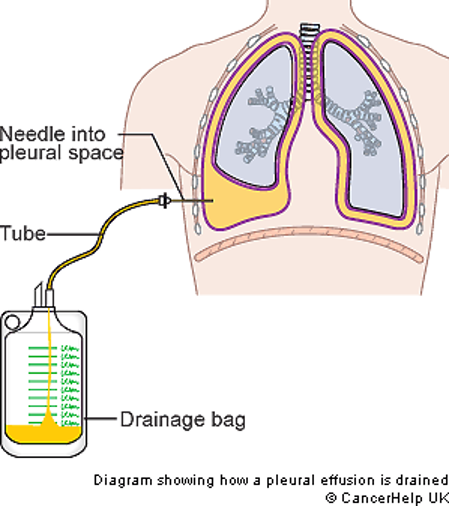

what is the:

costodiaphragmatic recess (CDR)...what is it a potential site for?

costomediastinal recess (CMR)

Potential pleural space located “between” the junction of diaphragm

and ribs

Potential site for pleural fluid accumulation

Potential pleural space located anteriorly “between” the junction of diaphragm and mediastimum

in picture you are looking from the top down...the CDR is wrapped around the 2 mickey mouse ears on the side where the ribs and diaphragm meet...the CMR is the small corners below the front circle on either side (slightly more yellow in color)

notice how the lung doesnt go all the way down and how there is a small corner where there can be an accumulation of fluid in the CDR

notice the cardiac notch in the CMR and how that can leave more space for the heart

the CDR is on the bottom of the lung in the kiddie-corner

the CMR is seen when you look down on the diaphragm from the top and see a small space in front

what is a thoracentesis? what do you want to avoid when you insert the needle? overall, where do you wanna put the needle?

below

- Procedure to remove fluid from pleural cavity

- Avoid damage to intercostal structures (and lung) when inserting needle

put the needle on the superior margin of the rib...avoids hitting the VAN's